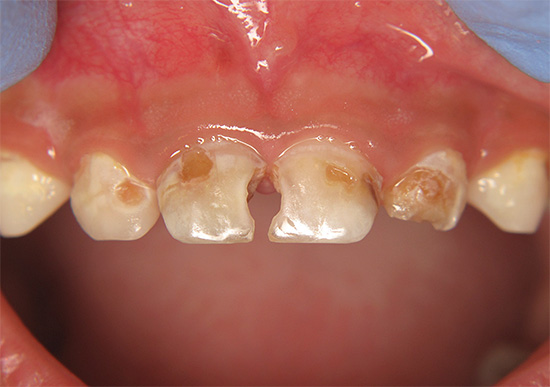

E questa foto mostra un altro esempio di come i denti sono stati colpiti carie generalizzata. Questa è una forma molto pericolosa della malattia, che minaccia una persona con la perdita di una parte significativa dei denti, la depulpazione (rimozione dei nervi) e l'installazione di corone:

Nell'aspetto e nella natura del corso, la carie delle bottiglie è quasi generalizzata. La principale differenza tra queste malattie è l'età delle persone che colpiscono: la carie in bottiglia si sviluppa principalmente nei bambini da 1 a 3 anni. Questo è spesso associato a un'immunità indebolita e malattie somatiche in tenera età.

Immagini della bottiglia della carie: